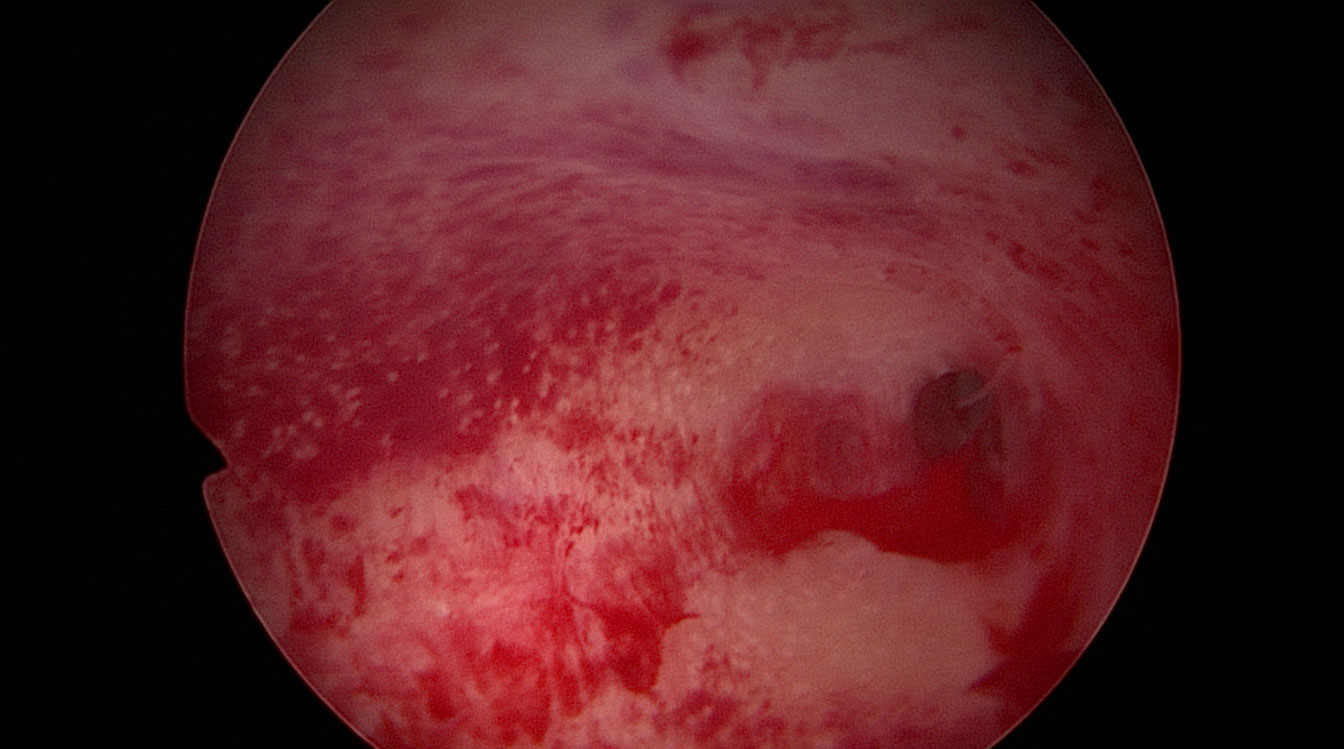

Țesutul cicatricial și aderențele din cavitatea uterină (fig. 7, 8) pot apărea după chiuretaje uterine, o intervenție chirurgicală uterină anterioară sau pot fi urmarea unei infecții. Prezența acestor aderențe oferă un mediu intrauterin nefavorabil implantării embrionului. Dacă aderențele sunt extinse la întreaga cavitate uterină pot determina absența menstruației. În timpul histeroscopiei aceste aderențe pot fi secționate cu ajutorul unor foarfeci speciali ce permit astfel refacerea cavității uterine (fig. 14). După operație, un mic balon poate fi introdus temporar în cavitatea uterină pentru a împiedica reapariția aderențelor sau pot fi utilizate geluri (ce conțin acid hialuronic) ce au același rol.